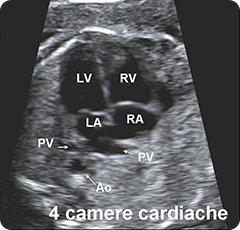

torace:

valutazione e visualizzazione della posizione del cuore e dei polmoni;

visualizzazione delle 4 cavità cardiache, dell'emergenza e incrocio dei

grossi vasi e della scansione 3VT